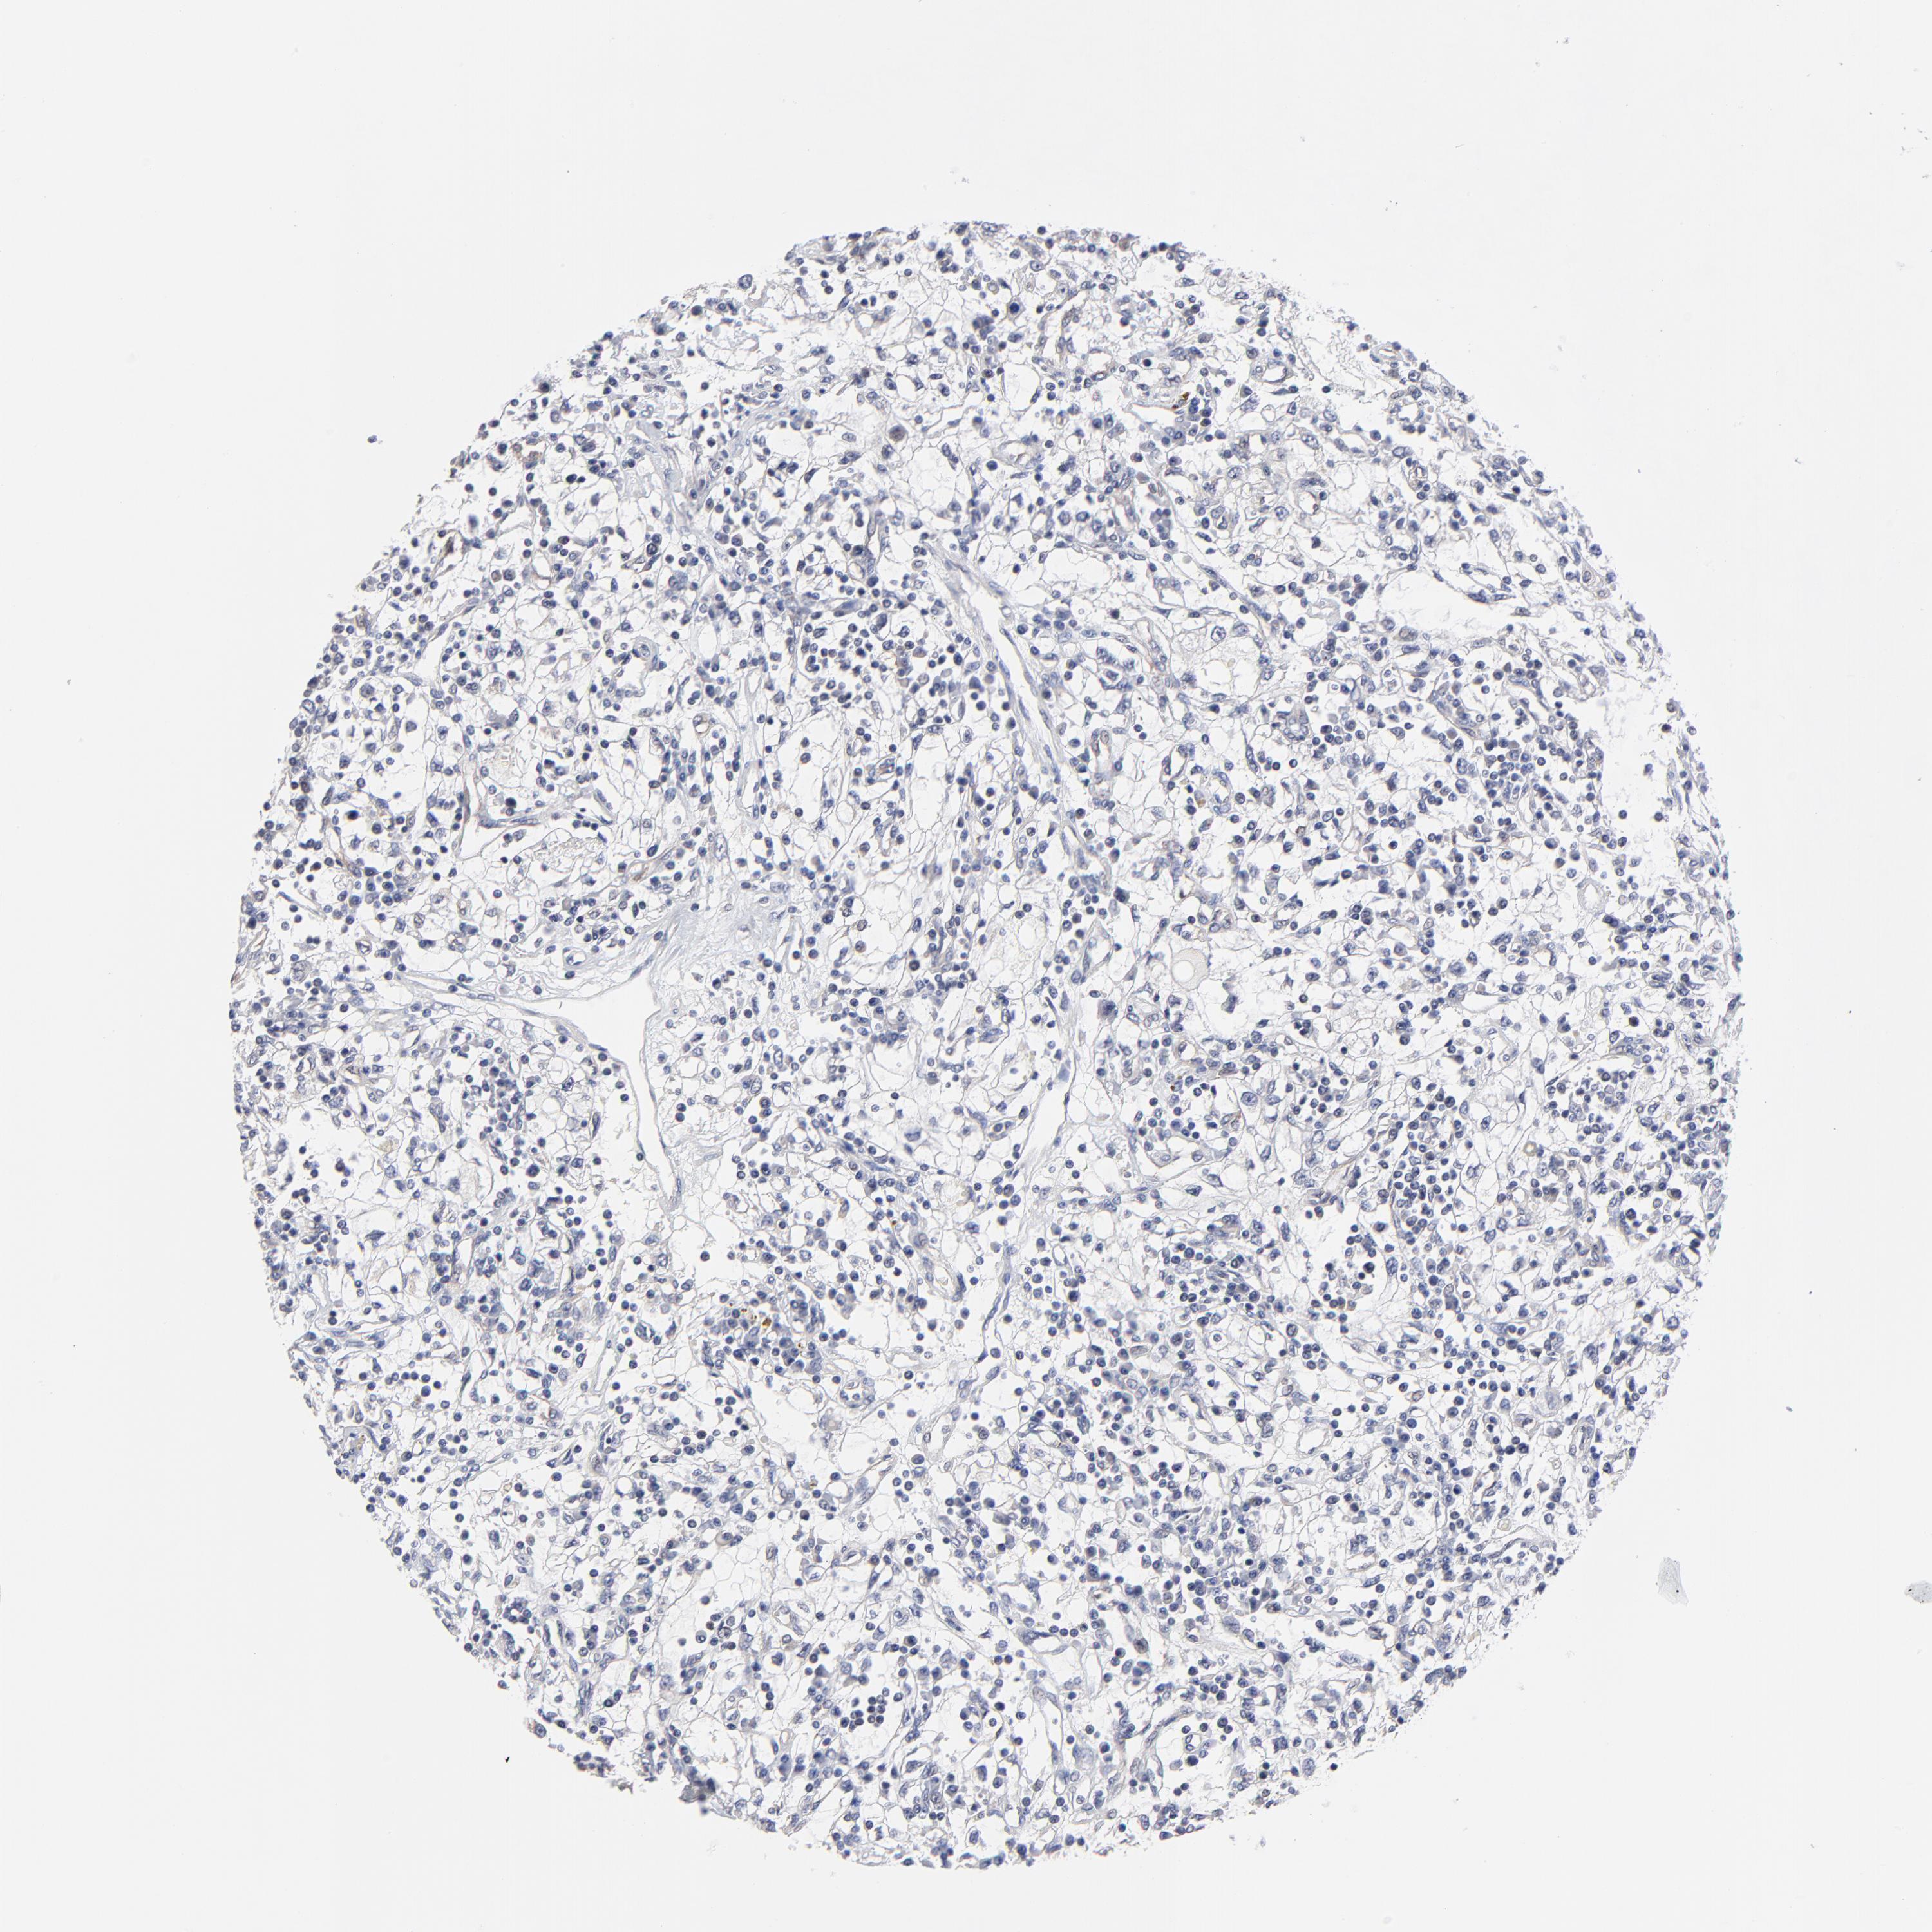

KIDNEY RENAL CLEAR CELL CARCINOMA (TCGA) - Interactive survival scatter ploti

The Survival Scatter plot shows the clinical status (i.e. dead or alive) for all individuals in the patient cohort, based on the same data that underlies the corresponding Kaplan-Meier plots. Patients that are alive at last time for follow-up are shown in blue and patients who have died during the study are shown in red.

The x-axis shows the expression levels (FPKM) of the investigated gene in the tumor tissue at the time of diagnosis. The y-axis shows the follow-up time after diagnosis (years). Both axes are complimented with kernel density curves demonstrating the data density over the axes. The top density plot shows the expression levels (FPKM) distribution among dead (red) and alive patients (blue). The right density plot shows the data density of the survived years of dead patients with high and low expression levels respectively, stratified using the cutoff indicated by the vertical dashed line through the Survival Scatter plot. This cutoff is automatically defined based on the FPKM cutoff that minimizes the p-score. The cutoff can be changed by dragging the vertical line or by entering a cutoff value in the square labeled "Current cut-off".

Under the Survival Scatter plot the p-score landscape (black curve; left axis) is shown together with dead median separation (red curve; right axis). Dead median separation is the difference in median mRNA expression between patients who have died with high and low expression, respectively. It is calculated as follows: median FPKM expression of dead patients with high expression - median FPKM expression of dead patients with low expression. This is intended to aid the user in visually exploring custom cutoffs and the associated p-scores and dead median separation.

Individual patient data is displayed and can be filtered by clicking on one or more of the category buttons on the top of the page. Categories describing expression level and patient information include: high, low, alive, dead, female, male and tumor stages. The scale of the x-axis can be toggled between linear and log-scale by clicking on the "x log" button. Mouse-over function shows TCGA ID, patient information and mRNA expression (FPKM) for each patient.

& Survival analysisi

Kaplan-Meier plots summarize results from analysis of correlation between mRNA expression level and patient survival. Patients were divided based on level of expression into one of the two groups "low" (under cut off) or "high" (over cut off). X-axis shows time for survival (years) and y-axis shows the probability of survival, where 1.0 corresponds to 100 percent.

FBXO8 is validated prognostic, high expression is favorable in Kidney Renal Clear Cell Carcinoma (TCGA)

Best expression cut offi

Based on the FPKM value of each gene, patients were classified into two groups and association between prognosis (survival) and gene expression (FPKM) was examined. The best expression cut-off refers the FPKM value that yields maximal difference with regard to survival between the two groups at the lowest log-rank P-value. Best expression cut-off was selected based on survival analysis .

When clicking on this number, the vertical dashed line indicating cut-off, the interactive survival plot, and the Kaplan-Meier curve will be adjusted to show results based on the best expression cut-off.

: 13.67

Average pTPM 18.0

Number of samples 521